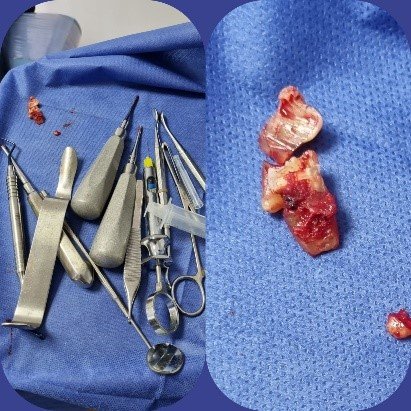

Cirugía bucal

Si tus “muelas del juicio” son un dolor de cabeza, de manera literal, te ofrecemos el tratamiento por elección, que es extraer tus muelas; ya sea para eliminar el dolor que estén ocasionando o para prevenir a futuro este tipo de malestares.

En el área de la cirugía bucal, también podemos tratar tus dientes que se encuentran “atrapados” en el hueso, ya sea para retirarlos por completo o para alinearlos por medio de un tratamiento de ortodoncia. No lo pienses más, y acude a nuestras instalaciones para realizar tu tratamiento.